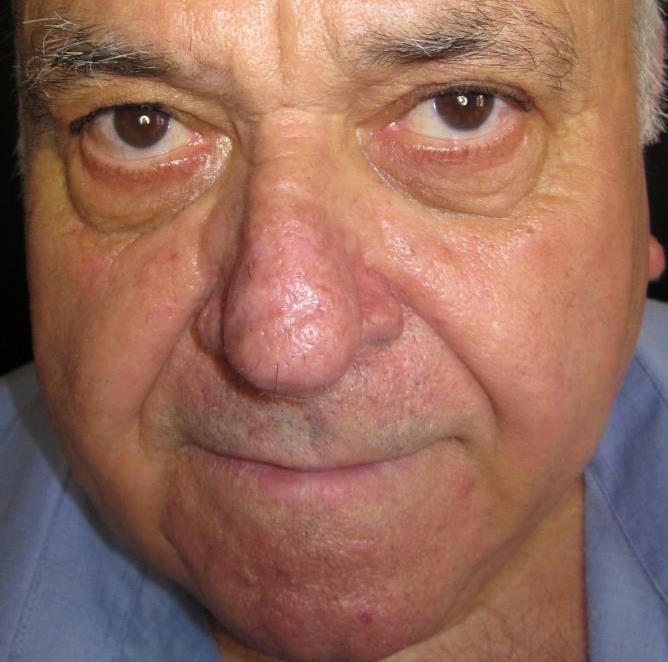

Trước

Hình ảnh minh họa

Sau

Hình ảnh minh họa